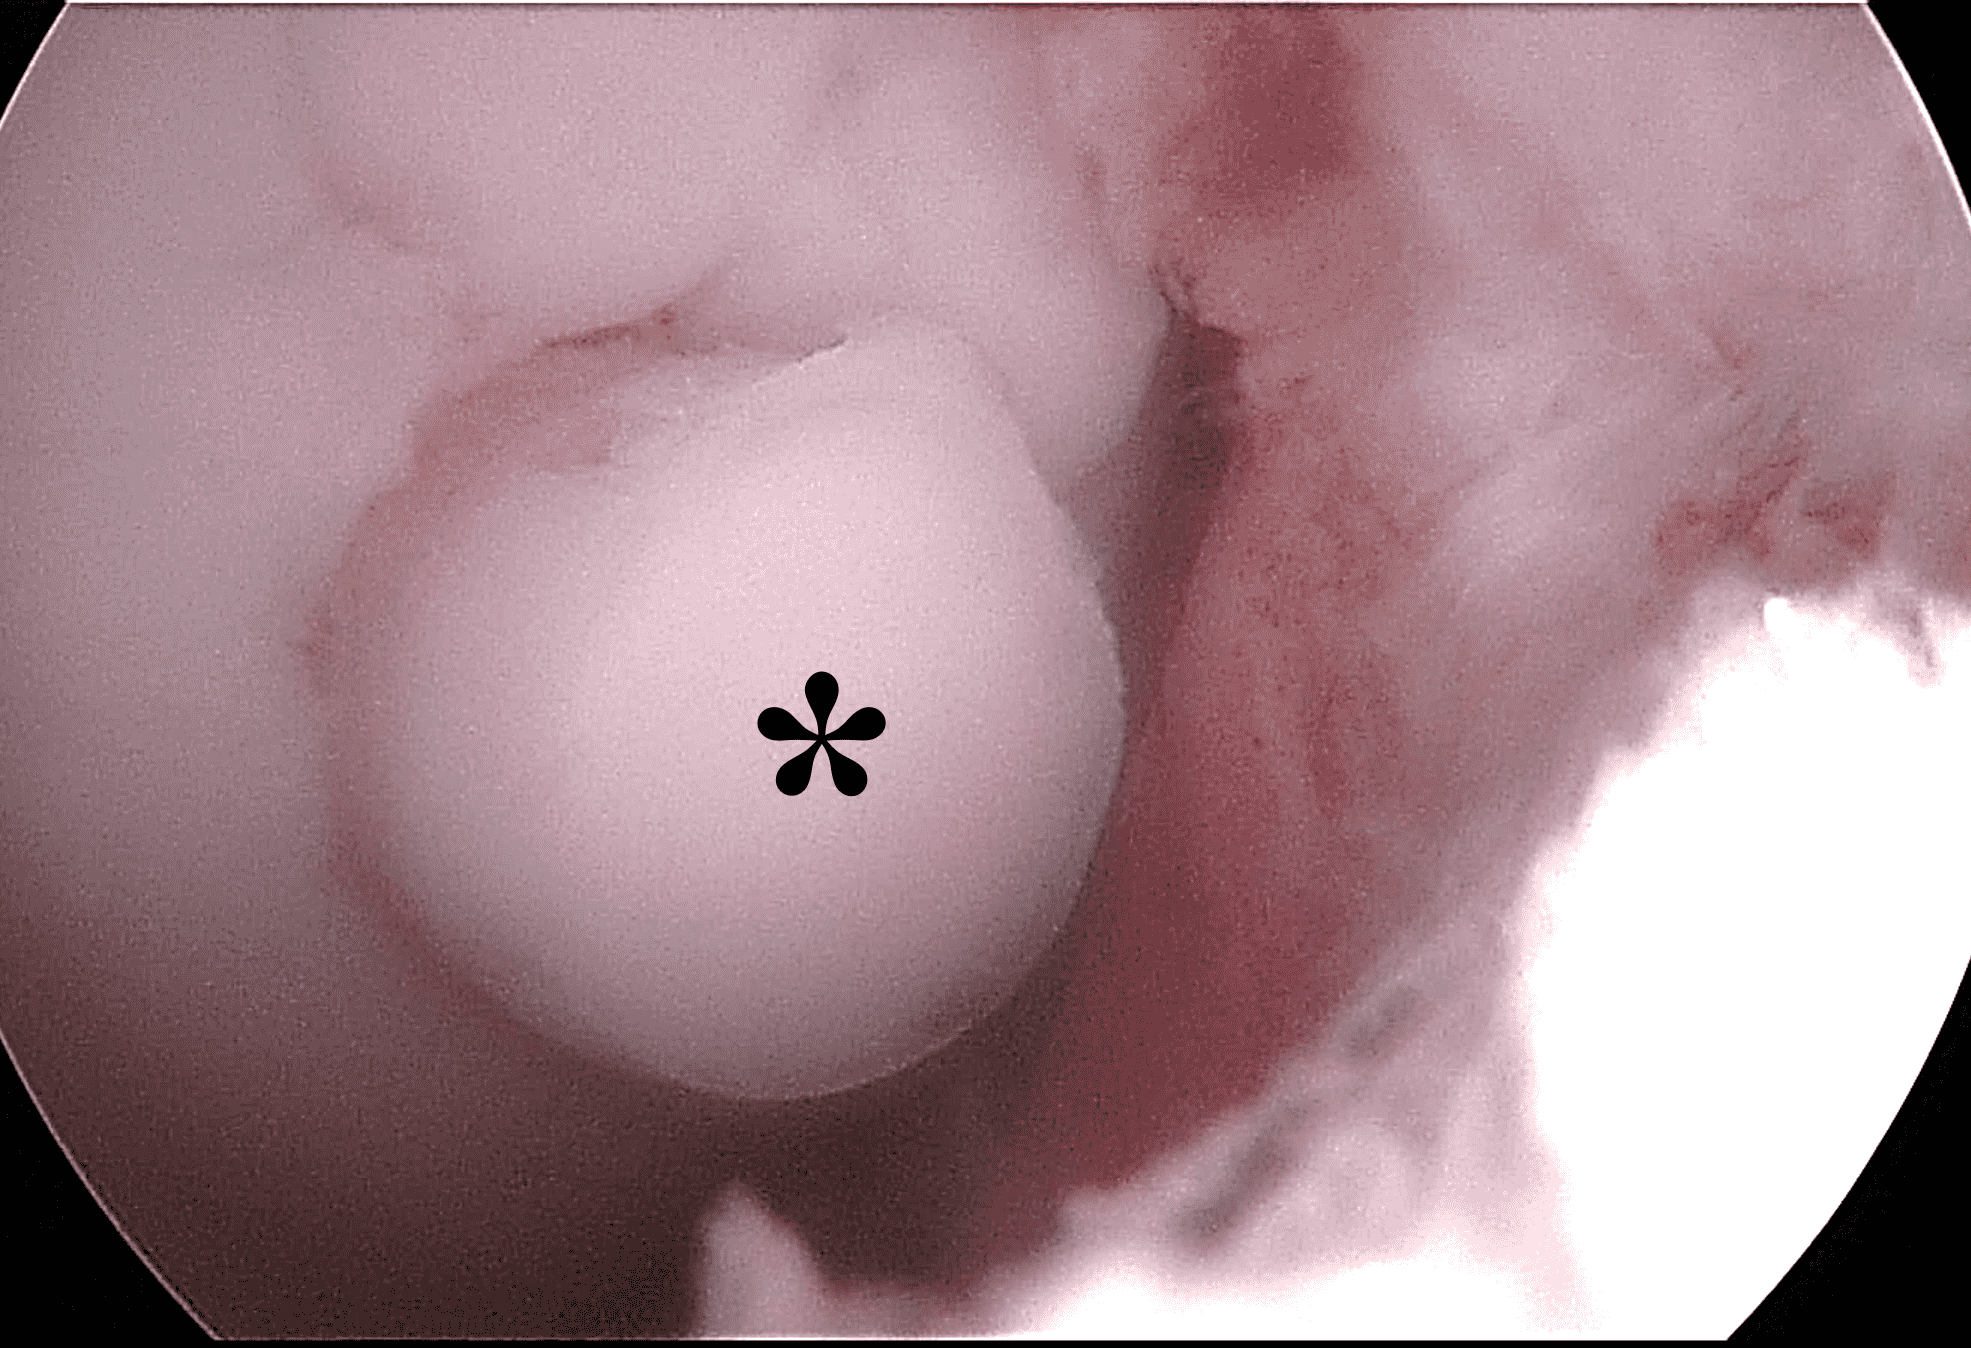

A frequent transfer performed in the knee is an arthroscopic osteochondral autograft, sometimes called a Mosaicplasty™ or OATS™ procedure. The donor sites are typically located along the outer or inner margins of the femoral trochlea, and are harvested with specific instrumentation (Figure 12A), producing cylinders 5-12 mm in diameter and 15-20 mm in length. The most common recipient sites are along the femoral condyles or patella. A donor site will typically backfill with trabeculae and marrow elements at its base and a thin layer of reparative fibrocartilage along its surface (Figure 13). Theoretically, the articular surface at the donor site is exposed to less stress compared to the treated region, but somewhere between 3 and 17% of patients develop symptoms at the donor site, usually relatively early after the procedure.23 Unfortunately, the MRI appearance of the donor site usually does not correlate with whether it is symptomatic or not.24

Figure 13: Osteochondral autograft donor site. (13A) Axial fat-suppressed fluid-sensitive image through a graft harvest site in the medial femoral trochlea. Fatty marrow has backfilled the deep portion of the donor site, which is faintly demarcated by granulation tissue (yellow arrows). Reparative fibrocartilage is present along the articular surface (red arrow). (13B) Arthroscopic image from a subsequent operation shows fibrocartilage capping the donor site (asterisk), which has a distinct color and surface compared to the surrounding normal cartilage.